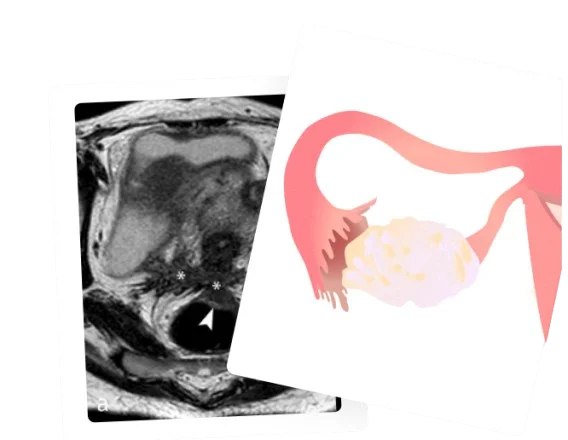

During the retrieval, you’ll be under sedation or anaesthesia, while the doctor performs a transvaginal ultrasound (similar to an AFC scan) and uses an ultrasound-guided needle to aspirate mature eggs from your ovaries.

Doctors visualise the ovaries using a transvaginal ultrasound (similar to your follicular scans). They then puncture the follicles (one at a time) to aspirate the follicular fluid, which contains the eggs.

During the retrieval, you will be under anaesthesia. In the surgical room, the doctor will have an ultrasound machine by their side, a transvaginal needle which is connected to 2 things – a vacuum for the “sucking” or the “aspirating” part and a set of test tubes to collect the follicular fluid.

Here’s how it goes: once the doctor identifies the ovaries on the ultrasound, they will insert the needle via the cervix, directly into the ovaries.

Once they identify the follicles on the ultrasound screen, they puncture them and use the power of the connected vacuum to suck out the follicular fluid.